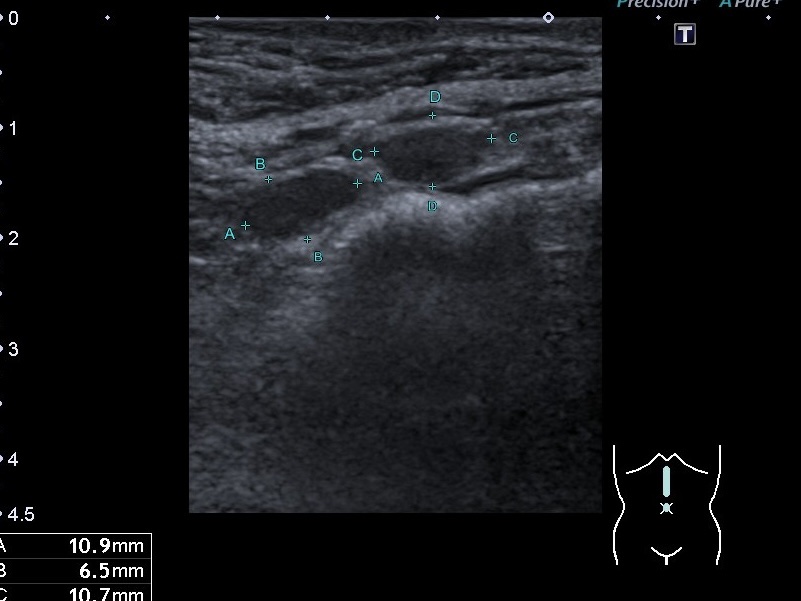

УЗД нервів та м’яких тканин. Якщо Ви думаєте, що дослідження нервів та м’яких тканин легко, то хочемо Вас розчарувати. Щоб...